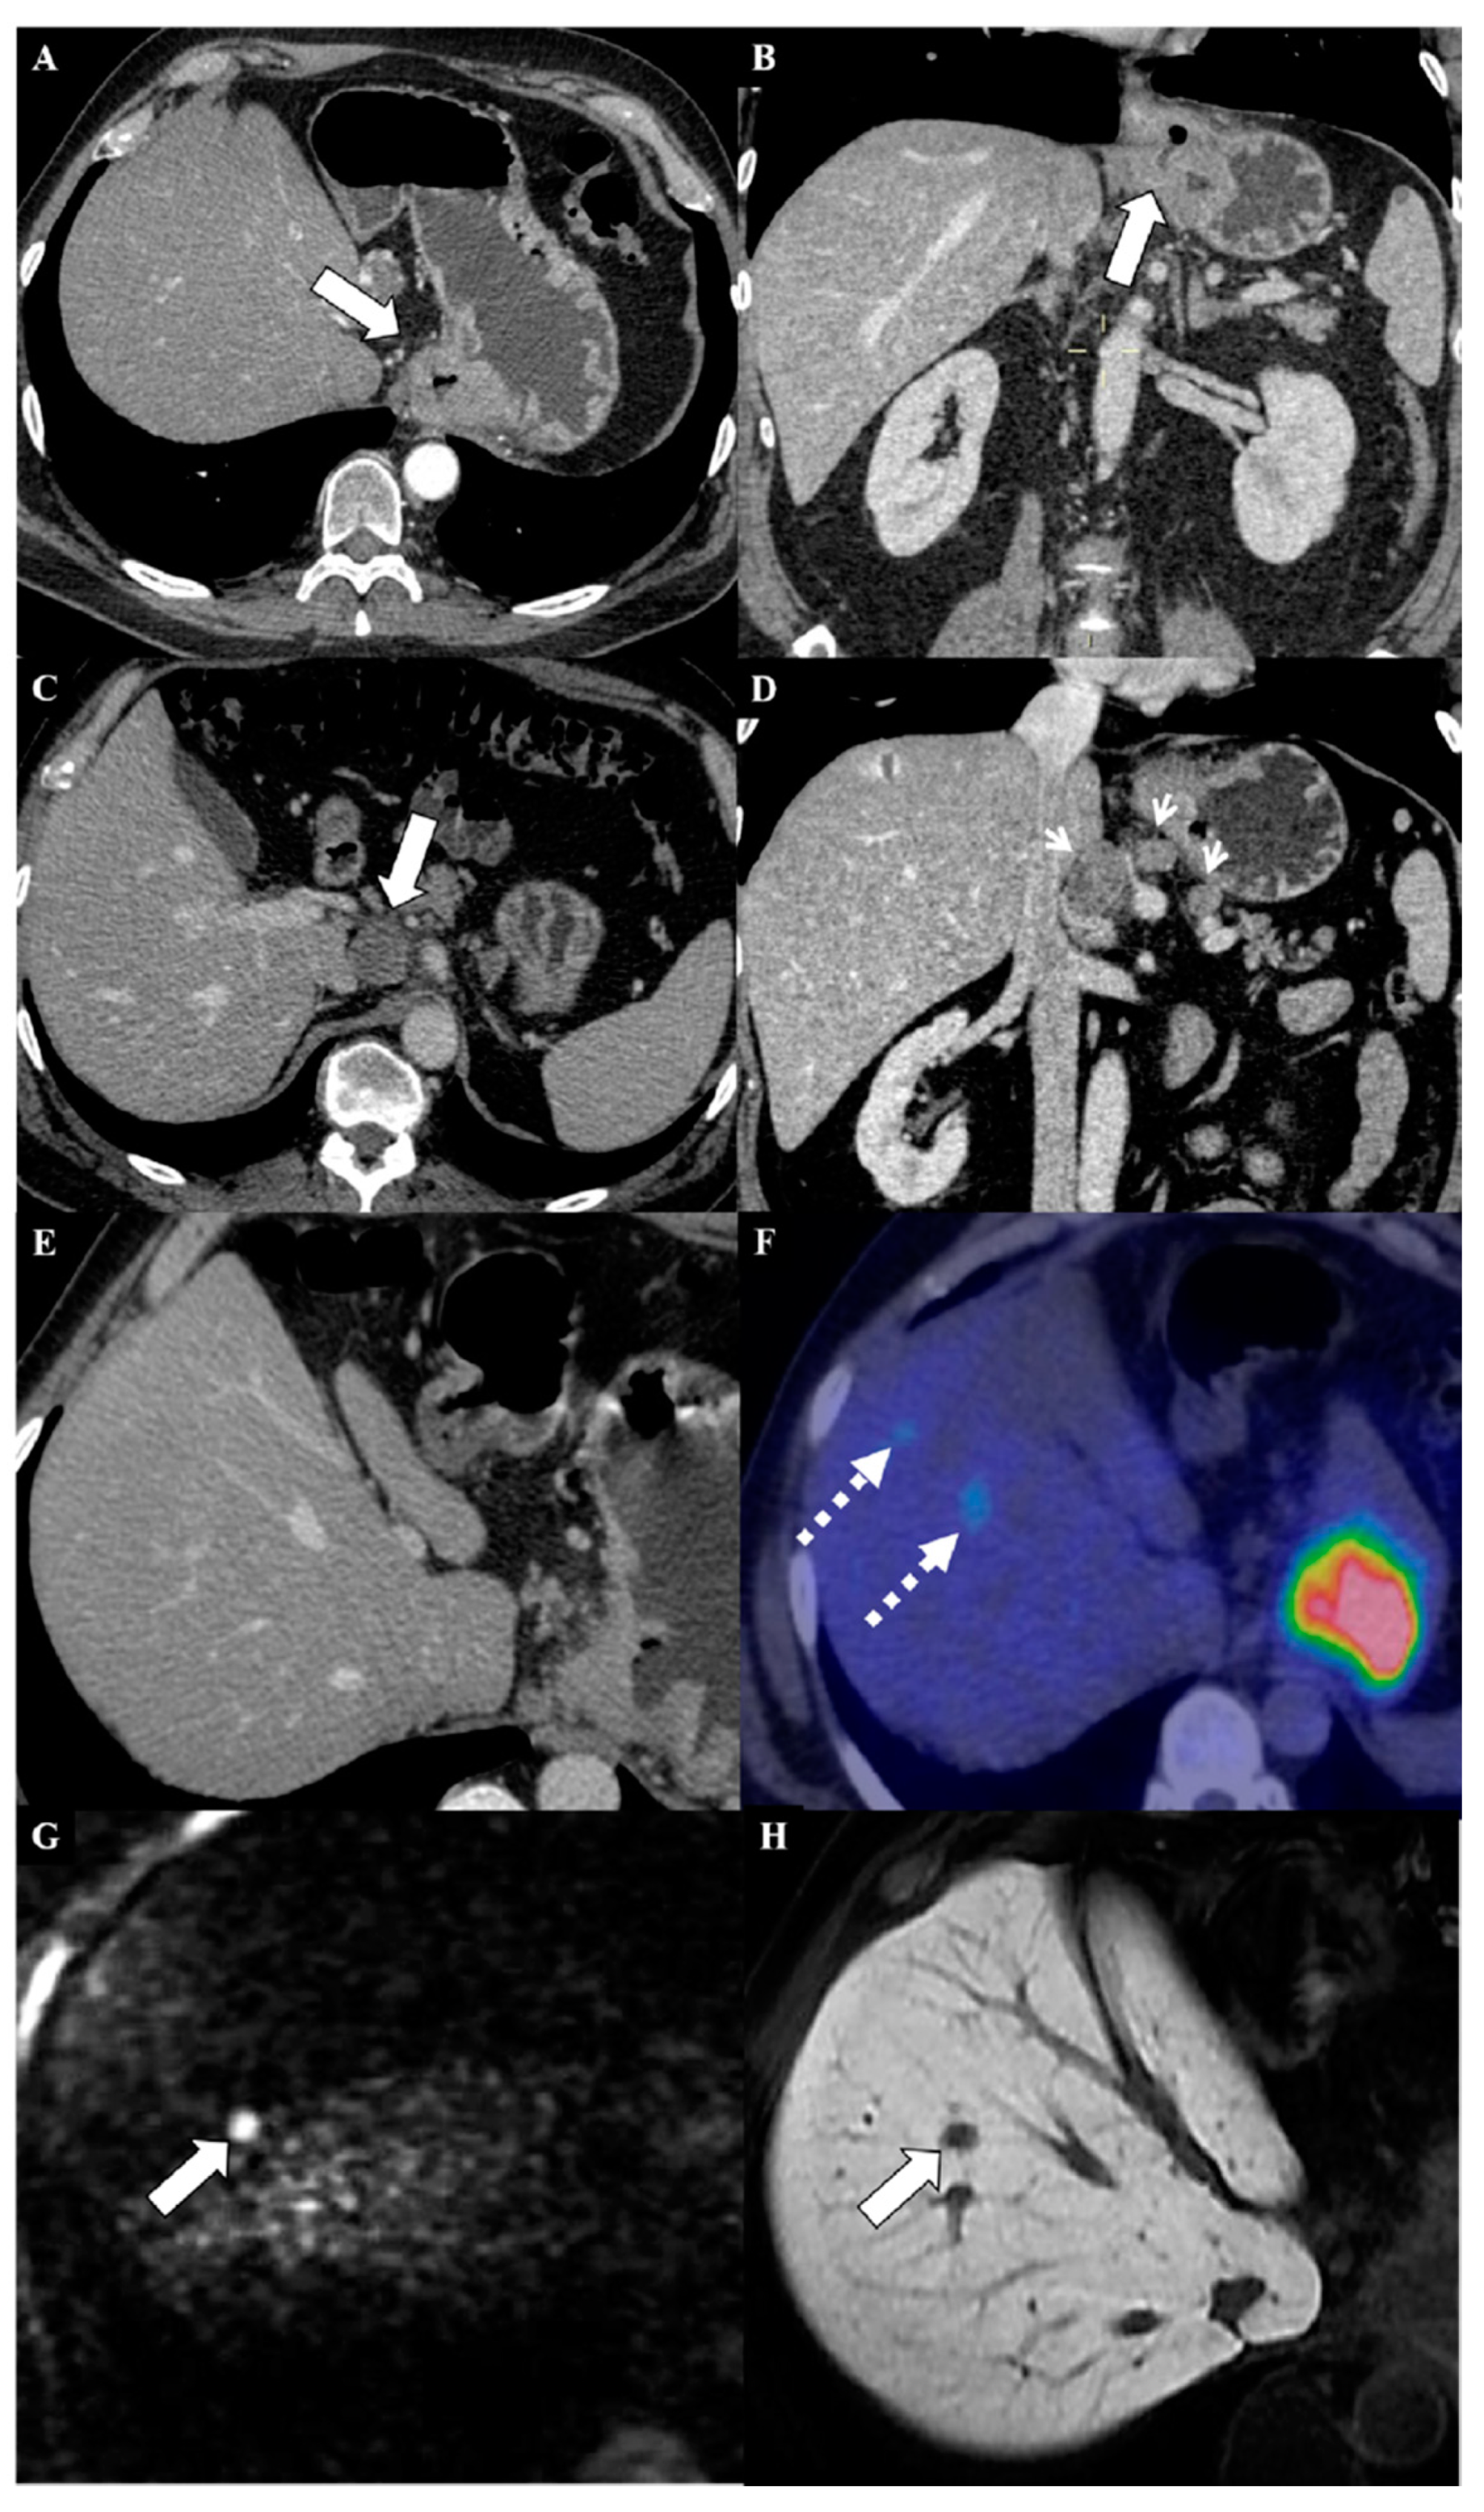

4. Magnetic Resonance Imaging of Metastases from Gastric Cancer

5. MRI in the Assessment of Peritoneal Metastases from Gastric Cancer

6. Magnetic Resonance Imaging in the Assessment of Liver Metastases from Gastric Cancer